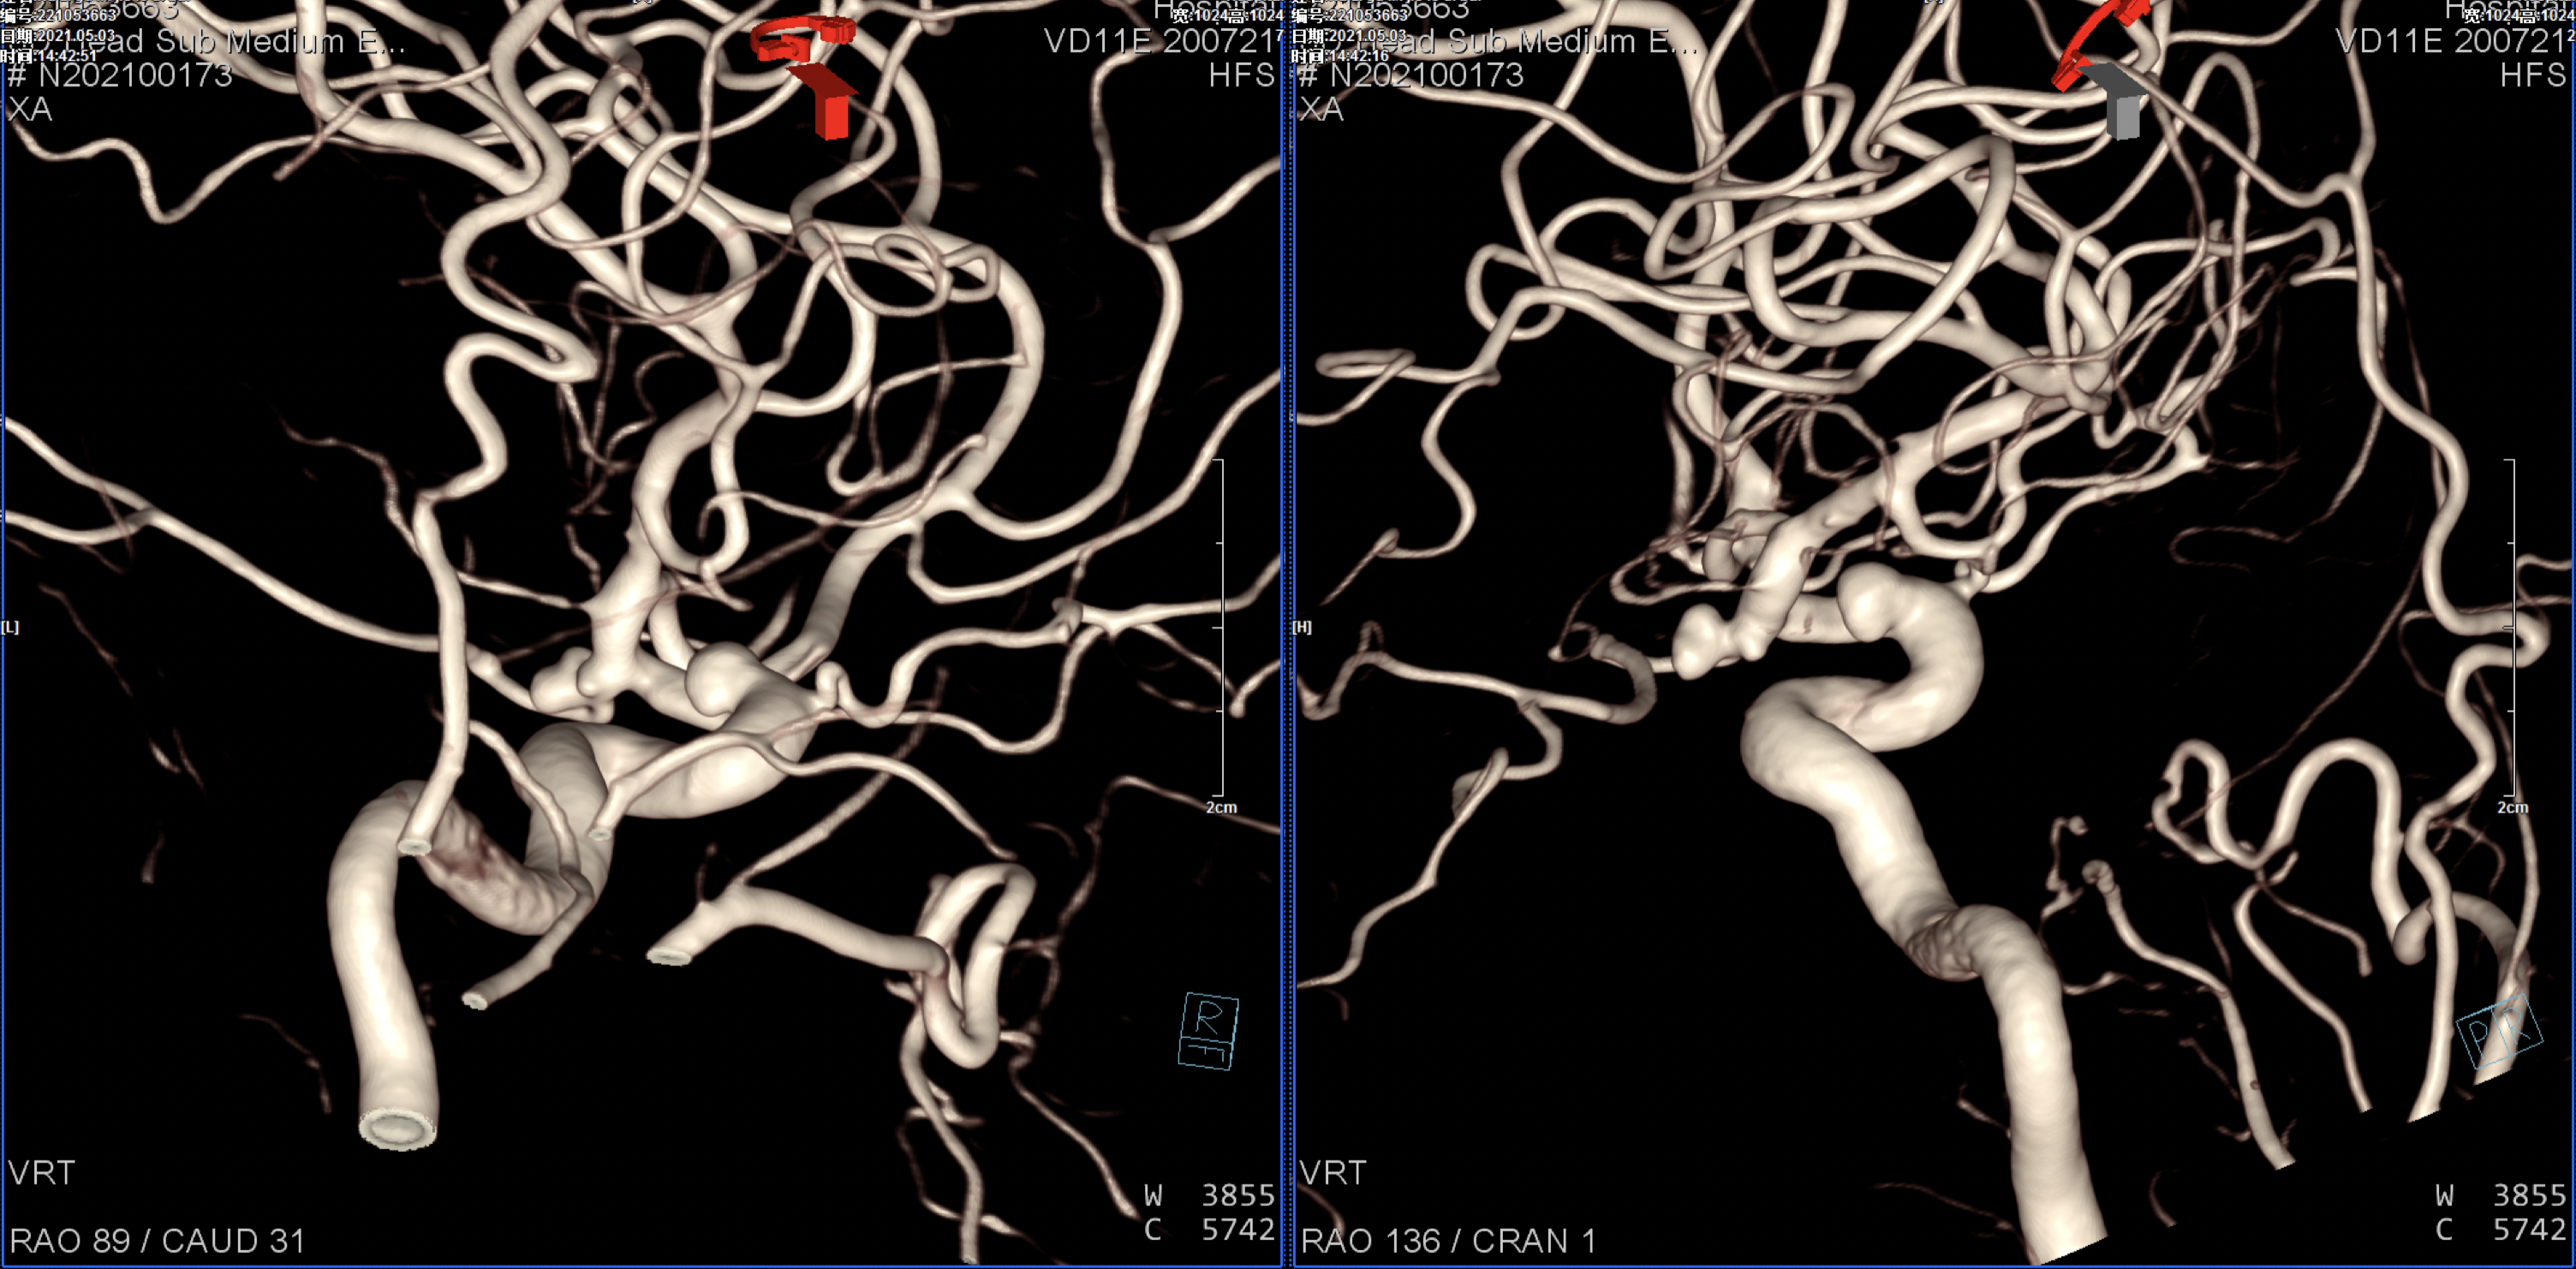

右侧颈内动脉正侧位造影:颈内动脉多发动脉瘤(眼动脉段及后交通段)。

右侧颈内动脉三维重建:颈内动脉多发动脉瘤(眼动脉段及后交通段)